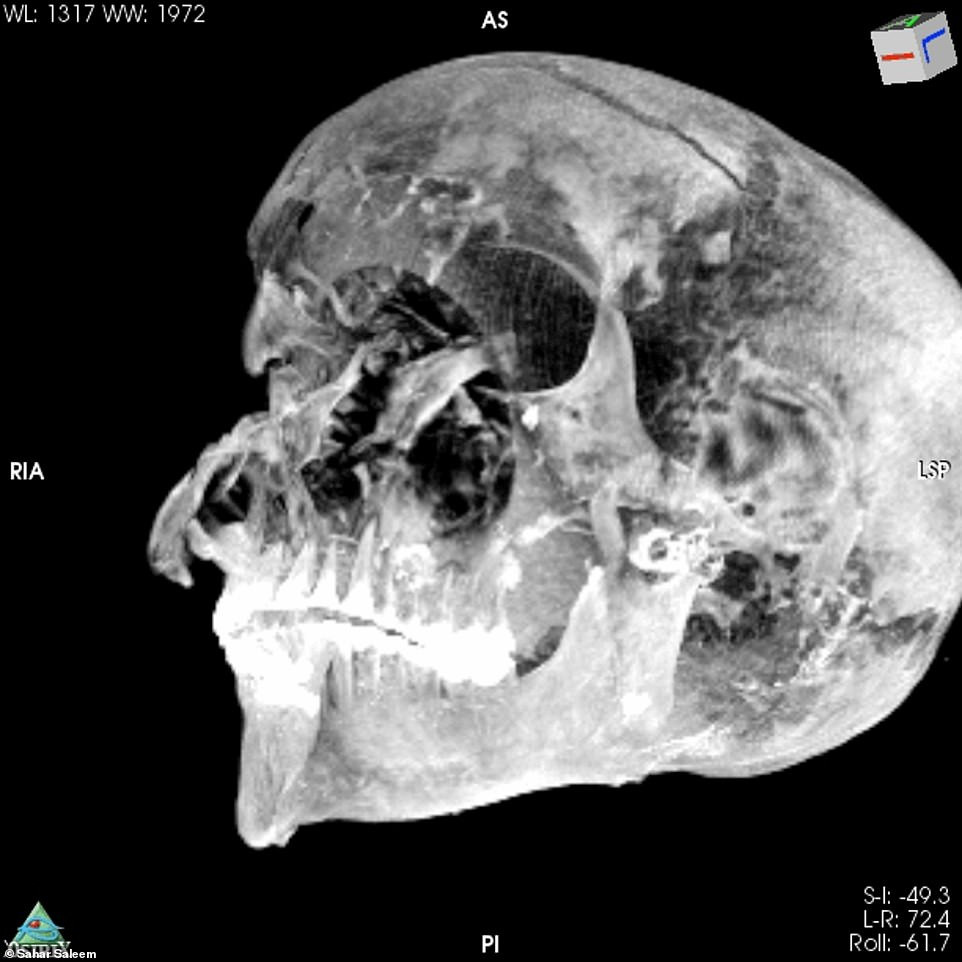

Cụ thể, kết quả chụp CT cho thấy phần mặt của xác ướp có nhiều vết thương. Những người thợ ướp xác cố gắng che những vết thương này khi bảo quản thi hài nhà vua.

Vào thời điểm qua đời, pharaoh Seqenenre Taa II có một vết thương lớn trên trán, vết cắt xung quanh mắt và má, một vết đâm ở đáy hộp sọ. Hộp sọ của nhà vua tách rời khỏi phần còn lại của thi hài.

Với những vết thương này, các chuyên gia nhận định pharaoh Seqenenre Taa II bị kẻ thù bao vây và tấn công từ nhiều phía. Họ sử dụng dao găm, rìu và giáo tấn công nhà vua Ai Cập đến chết.